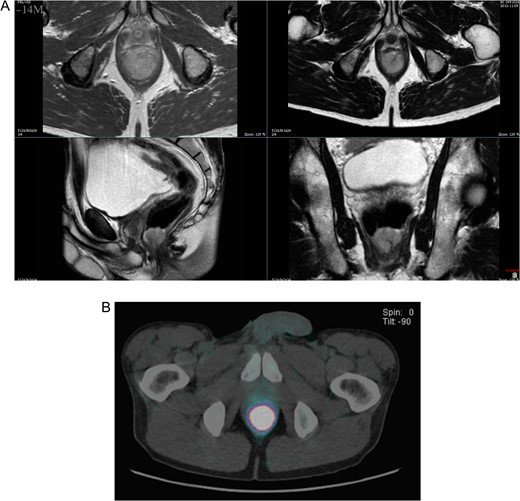

Proctoscopy confirmed the physical examination and showed a 3 cm bleeding villous polyp that originated above the dentate line. Endorectal ultrasound showed a fusion of all layers, infiltration of the sphincters and no suspect lymph nodes. Magnetic resonance imaging of the pelvis highlighted a high suspicion of internal sphincter infiltration and no inguinal or pelvic lymph nodes. Positron emission tomography–computed tomography (PET–CT) showed an intensely hypermetabolic lesion centred on the lower rectum (standardized uptake value (SUV) = 35.1) and no evidence of disease extension loco-regionally or at distance (Figs 1 and 2).

(A) T2-weighted axial, coronal and transverse MRI images, demonstrating the polypoid 3 cm anorectal mass. (B) PET–CT showed an intensely hypermetabolic lesion centered on the lower rectum.